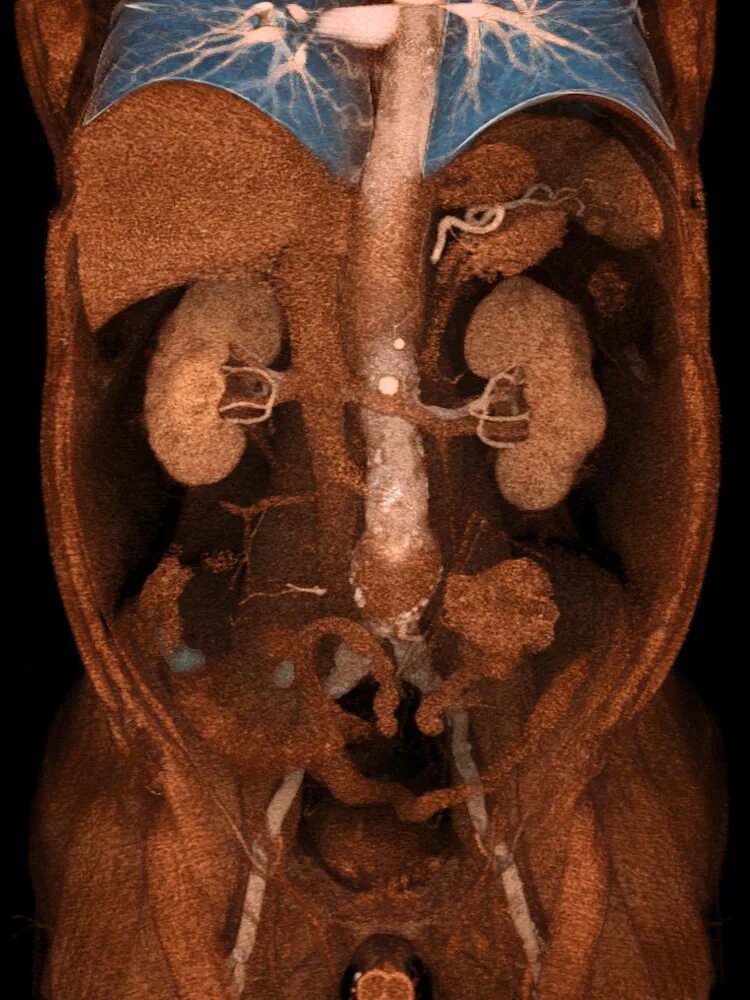

Мрт обп с контрастированием